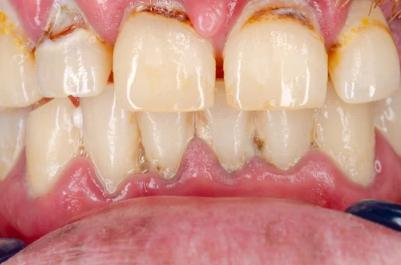

2. 잇몸이 붓고 붉다 – 정상적인 핑크빛이 아니다

염증이 심해질수록 잇몸은 단단함을 잃고 부풀어 오르며 붉게 변색됩니다.

- 치아 주변 잇몸이 탱탱하게 부어오름

- 밝은 분홍이 아닌 짙은 적색 또는 자주색

- 음식물 씹을 때 불편함 발생

▶ 부기와 발적(붉어짐)은 급성 치주염의 대표적인 징후로, 치료가 필요한 시점입니다.

4. 잇몸이 내려가고 치아가 길어 보인다 – 잇몸 퇴축 현상

잇몸뼈가 녹아내리면, 잇몸이 치아뿌리 쪽으로 물러나면서 치아가 길어 보이는 현상이 나타납니다.

- 거울로 보면 치아가 평소보다 길게 보임

- 잇몸 경계가 울퉁불퉁하고 균일하지 않음

- 찬물 마실 때 시림이 심해짐

▶ 치아가 길어지는 건 단순한 미용 문제가 아닌 치아지지 구조 약화의 증거입니다.

6. 고름이 나온다 – 잇몸 안쪽에 고름 주머니 형성

염증이 깊어지면 잇몸 속에서 고름이 생성되며, 압박 시 흰색 또는 노란색 분비물이 나올 수 있습니다.

- 잇몸이 부어 있고 누르면 고름 배출

- 냄새가 심하고 쓴맛 동반

- 고름이 자주 터지며 통증 반복됨

▶ 치근단 농양, 치주농양으로 이어질 수 있어 즉각적인 치료가 필요합니다.